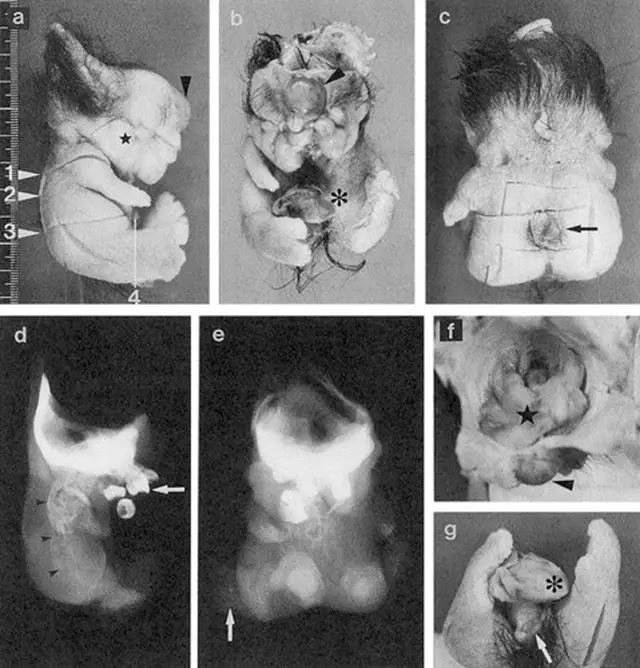

Brzmi jak scena z filmu grozy, ale to rzadki i opisany w literaturze medycznej przypadek. Podczas operacji guza jajnika u 25-letniej pacjentki w Japonii lekarze natrafili na niezwykle nietypową postać potworniaka: wewnątrz znajdowała się zorganizowana struktura z „głową, tułowiem i kończynami” – na tyle przypominająca miniaturową postać, że w publikacjach popularnonaukowych zaczęto o niej pisać jak o „lalkowym ciele”.

W opisie przypadku, opublikowanym w bazie National Library of Medicine, autorzy wskazują, że była to dojrzała postać fetiform teratoma (bywa też określana jako „homunculus”) – bardzo rzadki wariant potworniaka, w którym tkanki różnicują się w sposób wyjątkowo uporządkowany.

Badanie mikroskopowe potwierdziło obecność wielu typów tkanek, m.in. struktur oka, ucha, zębów, kości i szpiku, fragmentów przewodu pokarmowego i tchawicy, a także tkanki nerwowej opisywanej jako elementy mózgu/układu nerwowego.

Ten przypadek jest inny, bo autorzy opisują, że struktura miała wyraźnie zaznaczone osie „przód-tył” i „lewo-prawo” oraz układ, który przypominał elementy anatomiczne ułożone „sensownie” w przestrzeni. To właśnie sprawia, że fetiform teratoma bywa porównywany do „mini-ciała”, choć wciąż jest to guz, a nie rozwijający się płód.